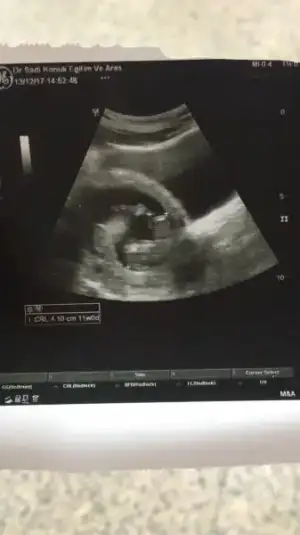

Teşekkür ederim hayırlı sı olsun sağlıkla ... bir rica da daha buluncam bu da 12 haftalık ken

Uzun boylu bir bebek. Erkek çocuk çabuk şekillenir derler. Ama bu işler hiç belli olmuyor. Kız da çikabiliyor bazen. Ben oğlumun cinsiyetini 3 aylıkken öğrenmiştim ve değişmedi. Doktor ne tahminde bulundu canım

Daha belli değil.. devlet hastanesi ne gidiyor um ben.. ve çok da ilgilenmiyor lar ne yazıkki şu an 12 bitti 13 teyim .. şu ara öğrenirim diye düşünüyorum.. öğrenir öğrenmez yazıcam teşekkür ederim ilgilendiğiniz için.. yinede yorum yapmak isteyenleri bekliyor um

Bu da daha net hali dediğim gbi belli değil henüz doktor a gidemedim